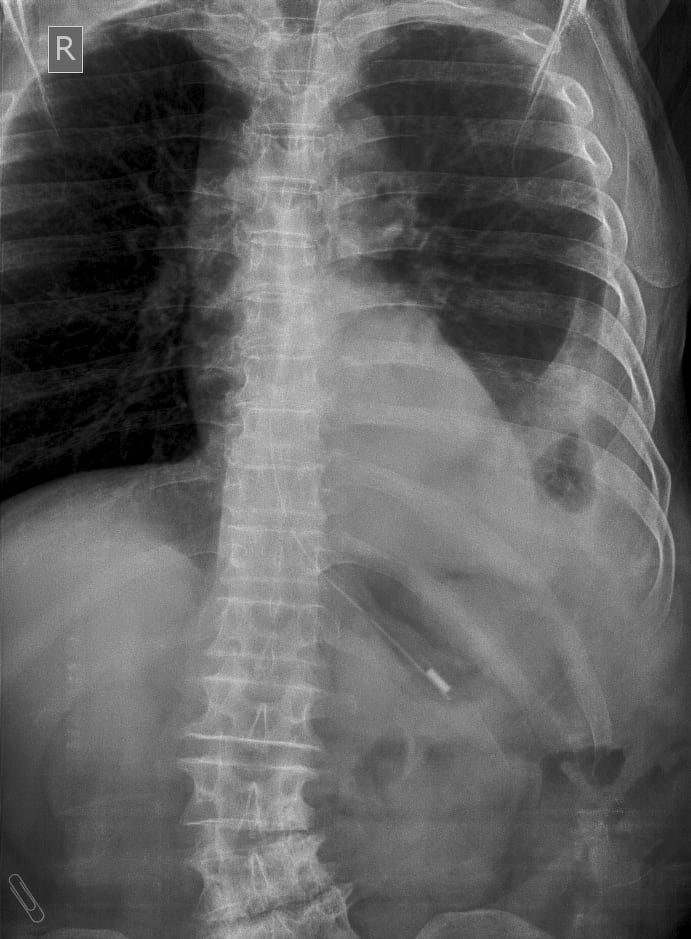

Xoắn dạ dày

» Thông tin: Nam giới – 60 tuổi.

» Lâm sàng: Đau bụng cấp + Nôn.